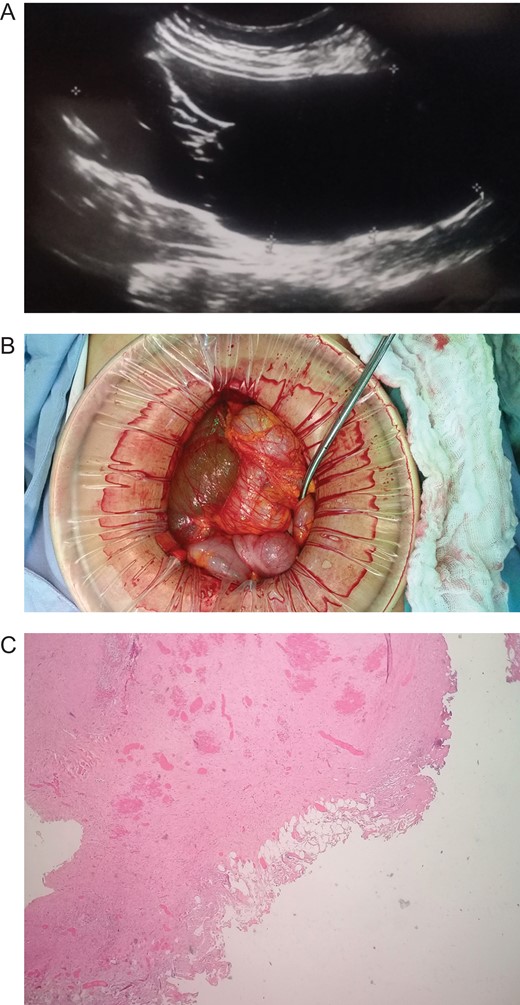

Patient is a 45-year-old female patient, with past medical history of gastritis. Six months before she sought medical attention, she was complaining of mild upper abdominal pain, however, due to her previous condition she was medicated with proton pump inhibitors assuming that the pain was due to her gastritis. In the last 3 months, she noticed a mass in her upper abdomen and the pain became more severe and started to affect her daily activities, thus she presented to a routine physical exam. No weight loss or other constitutional symptoms were noticed. Also no history of malignancy in her family was mentioned. On clinical examination, a 12 × 15 cm2 mass was discovered on her upper abdomen, mild pain was found on palpation but no tenderness was present. An abdominal ultrasonography revealed a 15 × 15 cm2 septate thin-walled giant cystic mass, it was anechoic and had a volume of ~735 ml. The cyst occupied most of the hepatorenal space and it was in intimate contact with the liver, right kidney and pancreas (Fig. 1A). Due to the size of the mass, CT was requested, it revealed well-defined 19.7 × 15 × 10 cm3 giant cyst, the cyst was located within the small bowel mesentery and it was in intimate contact with the liver, gallbladder, pancreas and right kidney (Fig. 2A). Nevertheless, the tomography could not rule out that the mass had some sort of communication with the bile duct or the pancreas. This is why a magnetic resonance cholangiopancreatography found that the cyst was attached but had no communication with the bile duct or the pancreas (Fig. 3A). CBC and blood work was normal.

(A) MRI, showing a giant cyst without communication with the bile duct or pancreas. (B) Mesenteric cyst adhesions to the gallbladder and liver.

Due to the size of the cyst and clinical condition surgery was planned. At laparotomy, a 19 × 15 × 10 cm3 mesenteric cyst was discovered (Fig. 1B), the cyst was near the root of the small bowel mesentery but did not compromise its main vessels, it had a yellowish appearance (Fig. 2B), and clear fluid was found within the cyst. Multiple adhesion were identified between the cyst wall and the transverse colon, liver, third portion of the duodenum and gallbladder. With these findings surgery was straightforward, complete resection of the cystic mass was performed, however, the cyst wall was completely attached to the body of the gallbladder and could not be resected without compromising it (Fig. 3B), so a cholecystectomy was performed as well. After this, the remainder of the procedure continued without any complication.